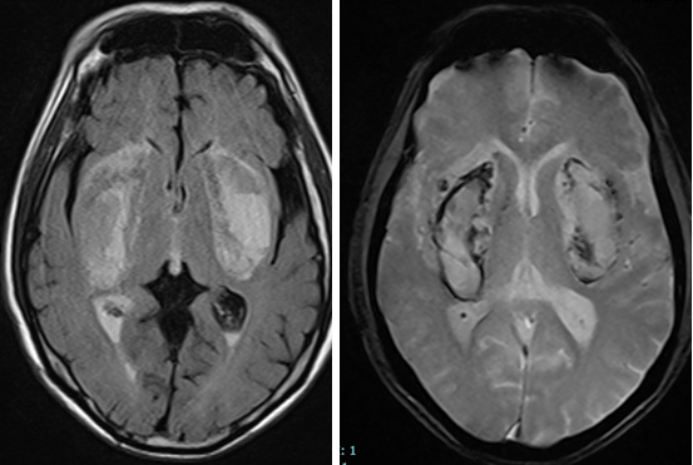

| Hình ảnh não tổn thương do tác dụng của methanol. Ảnh: BVCC/Vietnamnet. |

Kết quả chụp cộng hưởng từ sọ não cho thấy có tổn thương nhồi máu, hoại tử, chảy máu nhân bèo hai bên – dạng tổn thương não điển hình do ngộ độc methanol. Dù được hồi sức tích cực, lọc máu, thở máy nhưng tình trạng người bệnh vẫn rất nặng, hôn mê sâu, có nhiều nguy cơ lâm vào tình trạng sống thực vật.